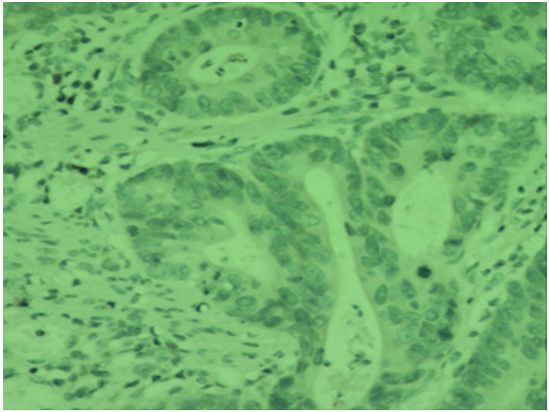

Id-1在结直肠癌组织中的阳性表达72.00%(36/50)明显高于癌旁组织24.00%(12/50),两者比较差异有统计学意义(χ2=23.431,P=0.000); MMP-9在结直肠癌组织中的阳性表达为78%(39/50),明显高于癌旁组织28.00%(14/50),两者比较差异有统计学意义(χ2=18.944,P=0.000);结直肠癌组织中LMVD表达(15.18±2.16)明显高于癌旁组织(5.24±1.09),两者比较差异有统计学意义(t=25.051,P=0.000),见图 1,表 1。

![]() 图 1 免疫组织化学法检测Id-1、MMP-9在结直肠癌癌旁与癌组织中的表达和LMVDFigure 1 Expression of Id-1,MMP-9 and LMVD in colorectal normal adjacent and colorectal tissues detected by IHC methodA: positive expression of Id-1 in colorectal normal adjacent tissues; B: positive expression of Id-1 in colorectal carcinoma tissues; C : positive expression of MMP-9 in colorectal normal adjacent tissues; D: positive expression of MMP-9 in colorectal carcinoma tissues; E: positive expression of LMVD markd by D-240 in colorectal carcinoma tissues (IHC ×200)表 1 Id-1、MMP-9在结直肠癌癌旁与癌组织中的表达和LMVDTable 1 The expressions of Id-1,MMP-9 and LMVD in colorectal normal adjacent tissues and colorectal carcinoma tissues

图 1 免疫组织化学法检测Id-1、MMP-9在结直肠癌癌旁与癌组织中的表达和LMVDFigure 1 Expression of Id-1,MMP-9 and LMVD in colorectal normal adjacent and colorectal tissues detected by IHC methodA: positive expression of Id-1 in colorectal normal adjacent tissues; B: positive expression of Id-1 in colorectal carcinoma tissues; C : positive expression of MMP-9 in colorectal normal adjacent tissues; D: positive expression of MMP-9 in colorectal carcinoma tissues; E: positive expression of LMVD markd by D-240 in colorectal carcinoma tissues (IHC ×200)表 1 Id-1、MMP-9在结直肠癌癌旁与癌组织中的表达和LMVDTable 1 The expressions of Id-1,MMP-9 and LMVD in colorectal normal adjacent tissues and colorectal carcinoma tissues